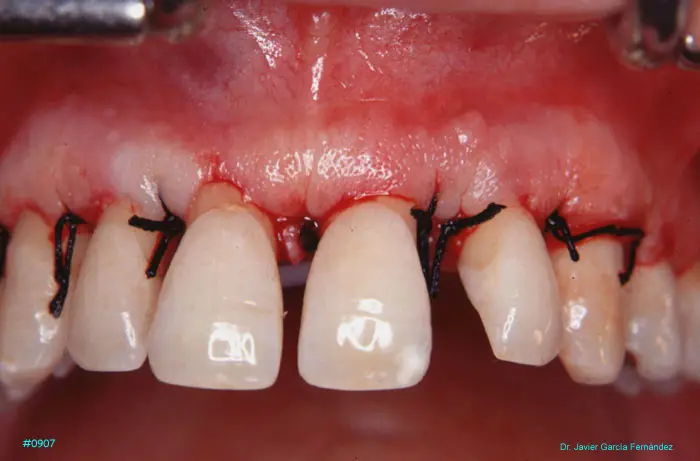

Atlas of Surgical Techniques in Periodontics. Chapter III. Atlas de Técnicas Quirúrgicas en Periodoncia